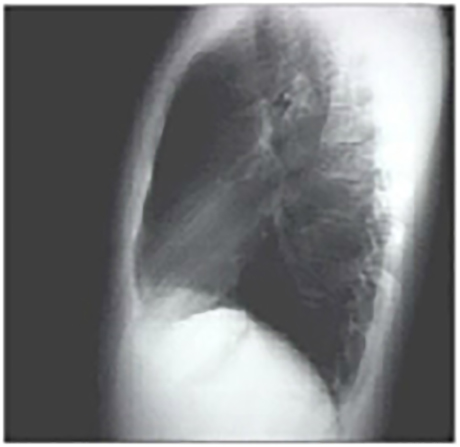

Lat

The lateral view is normal, with no evidence of chamber enlargement including the normal anterior shadow of the right ventricle and posteroinferior shadow of the left ventricle.